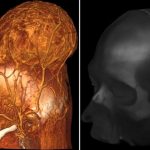

Con gran éxito neurocirujanos de Rusia extraen tumor cerebral maligno

Exitosamente, extirparon un enorme tumor cerebral maligno a una paciente de 37 años, el neurocirujano de Rusia Alexéi Ulitin y su equipo. El tumor...